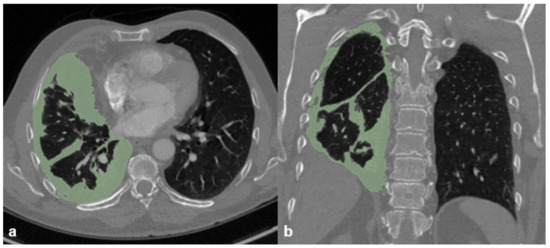

Tumor volume was assessed by outlining the tumor burden in the thoracic cage. Metastasis or lymph node metastasis were not measured (Figure 3).

Figure 3. Morphometric measurements of tumor volume on (a) axial and (b) coronal reformations.